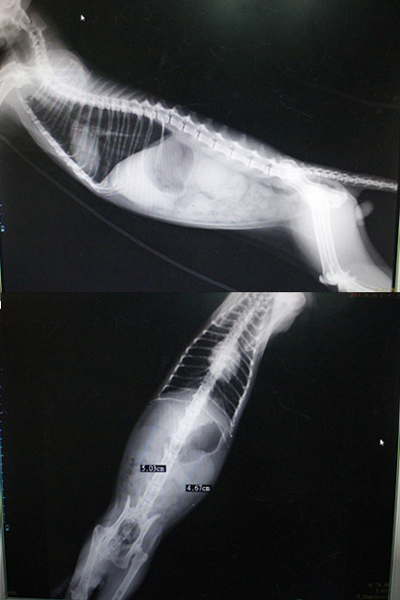

在打上點滴後先拍了x光片,

腎臟部分偏大,

一邊是5公分,一邊是4.6公分。

x光片顯示有胸水以及腹水,

心臟處變的比一開始大,